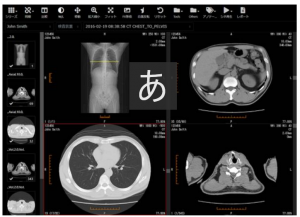

本製品は、CR や CT、MRI などの検査装置から発生するデジタルな医用画像データを保管、管理し、それらの画像を Web ブラウザで参照することができるソフトウェア。2018年の販売開始以来、Webブラウザベースの高速画像ビューアを搭載し、リーズナブルなコストで導入できることから、高い評価を得ている。